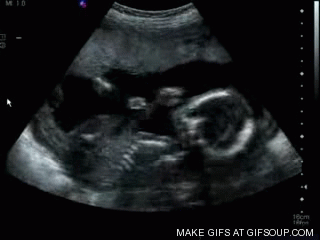

Ultrasound can be used to create an image of a baby in the womb or of other structures in the human body.

Ultrasound travels into the body and some is reflected at the boundary of different tissues.

The reflected ultrasound arriving back at the detector at different times can build up a picture of the depth of the different tissues.